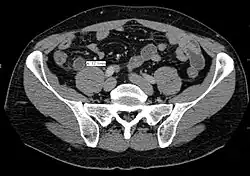

A fecalith marked by the arrow that has resulted in acute appendicitis.

Where it is readily available, computed tomography (CT) has become frequently used, especially in people whose diagnosis is not obvious on history and physical examination. Although some concerns about interpretation are identified, a 2019 Cochrane review found that the sensitivity and specificity of CT for the diagnosis of acute appendicitis in adults was high.[63] Concerns about radiation tend to limit use of CT in pregnant women and in children, especially with the increasingly widespread usage of MRI.[64][65]

The accurate diagnosis of appendicitis is multi-tiered, with the size of the appendix having the strongest positive predictive value, while indirect features can either increase or decrease sensitivity and specificity. A size of over 6 mm is both 95% sensitive and specific for appendicitis.[66]

However, because the appendix can be filled with fecal material, causing intraluminal distention, this criterion has shown limited utility in more recent meta-analyses.[67] This is as opposed to ultrasound, in which the wall of the appendix can be more easily distinguished from intraluminal feces. In such scenarios, ancillary features such as increased wall enhancement as compared to adjacent bowel and inflammation of the surrounding fat, or fat stranding, can be supportive of the diagnosis. However, their absence does not preclude it. In severe cases with perforation, an adjacent phlegmon or abscess can be seen. Dense fluid layering in the pelvis can also result, related to either pus or enteric spillage. When patients are thin or younger, the relative absence of fat can make the appendix and surrounding fat stranding difficult to see.[67]

In general, plain abdominal radiography (PAR) is not useful in making the diagnosis of appendicitis and should not be routinely obtained from a person being evaluated for appendicitis.[70][71] Plain abdominal films may be useful for the detection of ureteral calculi, small bowel obstruction, or perforated ulcer, but these conditions are rarely confused with appendicitis.[72] An opaque fecalith can be identified in the right lower quadrant in fewer than 5% of people being evaluated for appendicitis.[48] A barium enema has proven to be a poor diagnostic tool for appendicitis. While failure of the appendix to fill during a barium enema has been associated with appendicitis, up to 20% of normal appendices do not fill.[72]